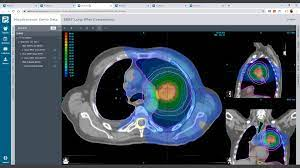

ProKnow提供了一些工具,可以根据患者个人和患者群体的需求,在评分卡中定制临床指标和目标。评分卡有助于推动标准化、提高质量、消除不需要的变动,并证明报销的合理性。

该平台还支持有效性对比,帮助您基于数据,来制定决策,选择最适合您的技术、模式和协议。该解决方案支持所有计划系统和治疗模式,包括IMRT、VMAT、传统的3D外照射、质子、机器人、螺旋弧和近距离放疗。